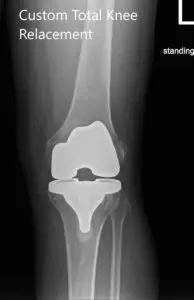

The implant used: Custom femoral implant with a custom tibial tray, with 8-mm polyethylene insert, with custom 35-mm x 7-m patellar implant.

Postoperative X-ray images of the left knee in AP and lateral view.